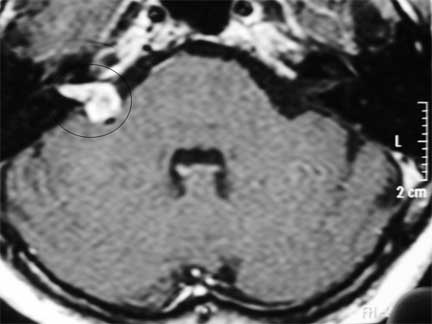

NEURINOMA DEL ACÚSTICO EN PACIENTE DE EDAD AVANZADA CON PÉRDIDA AUDITIVA Y TRASTORNO DEL EQUILIBRIO. EN VISTA DEL ALTO RIESGO PARA CIRUGÍA ABIERTA. SE INDICA RADIOCIRUGÍA

Neurinoma del nervio acústico. El neurinoma está inscrito en un círculo.